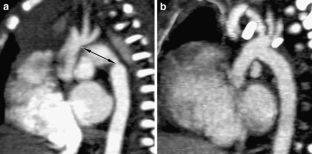

Fig. 1